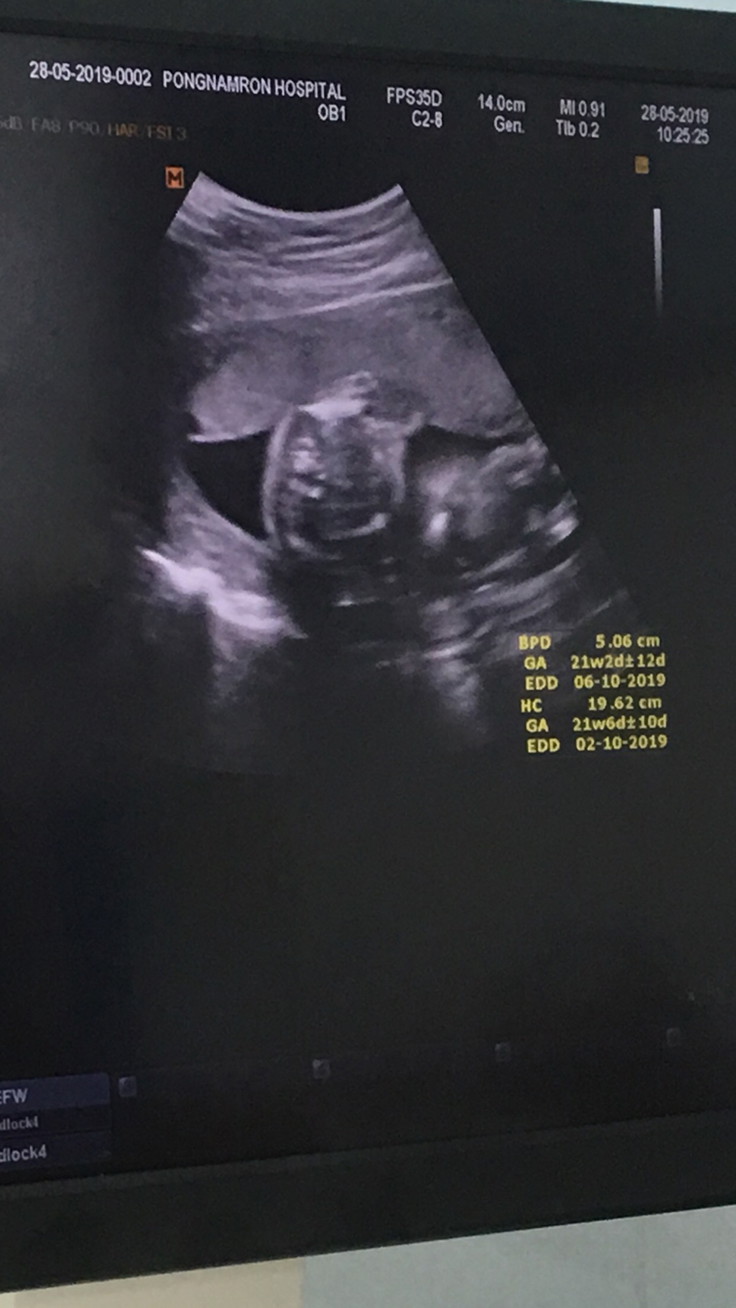

21 สัปดาห์ค้ะ